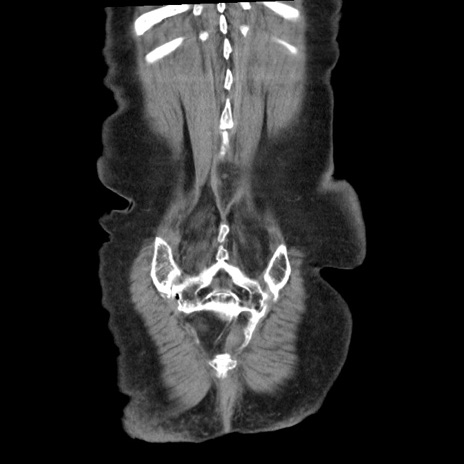

矢状断像